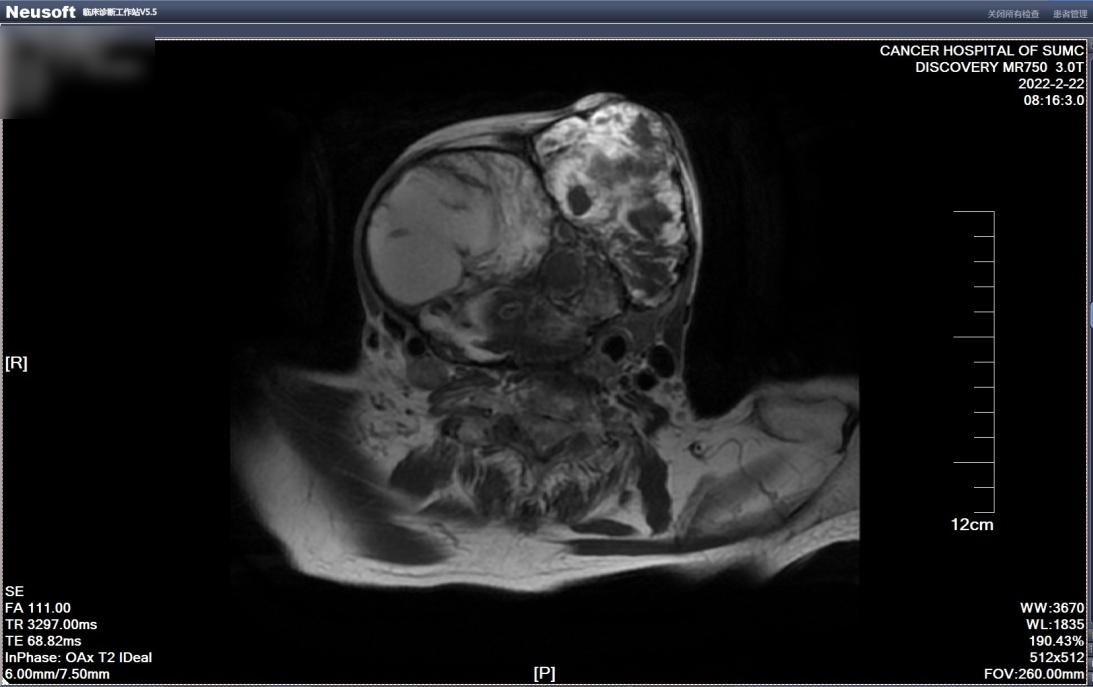

经入院检查发现,患者颈前区巨大团块肿物大小约20×18×12cm,质硬,界不清,表面皮肤可见破溃出血,范围大小约3.0×3.0cm。入院后予完善相关检查,患者磁共振检查提示:甲状腺多发结节、肿块,考虑结甲性甲状腺肿并恶变,右颈多发淋巴结肿大。

磁共振图像